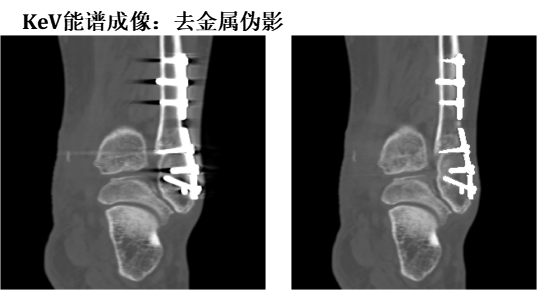

三、能谱单能成像

利用独有的35keV到39kev的低keV图像增加不同组织结构之间的对比 ,有利于等密度病变和小病灶的早期探查、发现,有助于发现乏血供性小肿瘤,显示肿瘤细小供血动脉等 ,可为手术提供依据,如复查栓塞术后效果 ,非常优秀的显示静脉系统,优化动脉成像等。